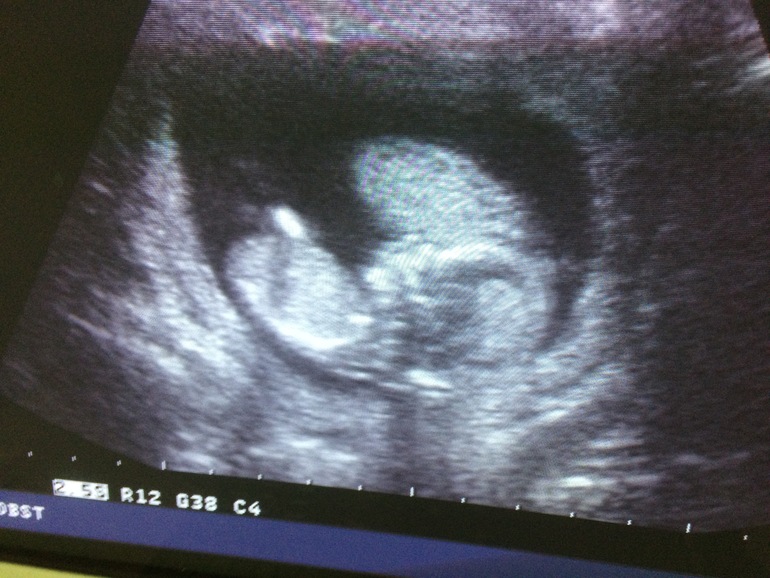

Девочки,привет.🍓 я схожу с ума. Не могу расслабиться,и наслаждаться своим положением. Срок у меня 13 н 4д,прошла первый скрининг,пока есть результаты только узи,все хорошо,по крови ещё не получила результаты. Я сделала уже 5 узи за все время,походу надо покупать абонемент.😂 в день когда меня чуть меньше обычного тошнит,или чуть меньше болит грудь,у меня начинается паника.. у меня была в 2015 году анэмбриония,в декабре 2018 бхб,сказывается это на моем эмоциональном состоянии. Я очень переживаю за малыша,боюсь что не дай Бог пойдёт что-то не так.. Хоть и срок уже не совсем маленький,и опасность намного меньше,и в прошлые бер вообще не было даже эмбриона,мне все равно страшно. Так же у меня тонус,плюс ставили полное предлежание. Это отдельная история. Сначала сказали краевое,потом полное,а вчера сказали все нормально,никакого краевого даже нет.. 3 узи,3 разных мнений.. Это вообще нормально?! Вчера показал малыш свой писюн на экране,у нас мальчик.😍 конечно это ещё не точно,но такое богатство у девочки врятли может быть.😂 ещё в мазке у меня повышены лейкоциты,ставлю гексикон. И полип вылез на шейке,из-за него кровило чуть чуть неделю назад,больше слава Богу не кровило.. Так вот девочки,как успокоиться? Никому не говорим про беременность,потому что боимся даже произносить.. Все эти результаты анализов в принципе не страшны,я очень надеюсь,что малыш наш родится здоровенький,в срок. Ведь если сейчас все хорошо,то надеюсь так и будет.. Фото нашего сладкого пупсика,и ещё почему-то не спросила у врача,что это за белое пятно за малышом?